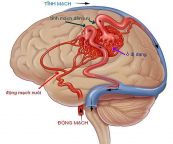

Chụp động mạch đầu và cổ là thủ tục X-quang sử dụng thuốc nhuộm và máy ảnh đặc biệt (fluoroscopy) để chụp ảnh lưu lượng máu trong các mạch máu của đầu và cổ. Chụp động mạch cổ (chụp động mạch cảnh) có thể được sử dụng để xem xét các động mạch lớn ở cổ dẫn đến não. Bài viết dưới đây sẽ nói rõ hơn về phương pháp xét nghiệm này, mời các bạn tham khảo!